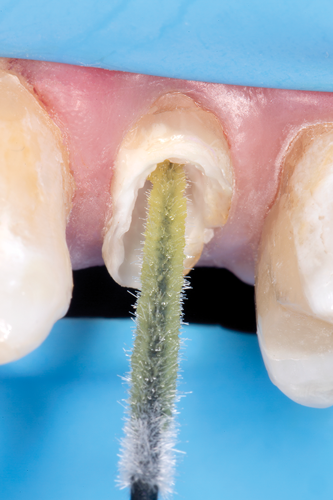

After completion of the endodontic treatment and crown lengthening to develop an ideal ferrule effect (Figure 3 through Figure 5) a diagnostic wax-up was fabricated to an ideal coronal preparation geometric shape, dimension, and height for the anticipated final composite core buildup (Figure 6). A clear polyvinyl siloxane (PVS) impression material was injected into a nonperforated tray, placed over the diagnostic wax-up, and then put into a pressure pot with cold water for 5 minutes. This procedure is aimed at reducing the potential for the formation of voids and bubbles in the impression material (Figure 7 and Figure 8). A small opening was made above the tooth to be restored using a tapered diamond bur (6847) (Figure 9). It is important to clean the internal surfaces with a microbrush to prevent silicone debris from integrating into the flowable material. Prior to the restorative procedure, a diagnostic wax-up was fabricated to the anticipated extracoronal contours for development of the final crown (Figure 10).

Fig 9. A small opening was made above the tooth to be restored using a tapered diamond bur; the internal surfaces should be cleaned with a microbrush to prevent silicone debris from incorporating into the flowable material.